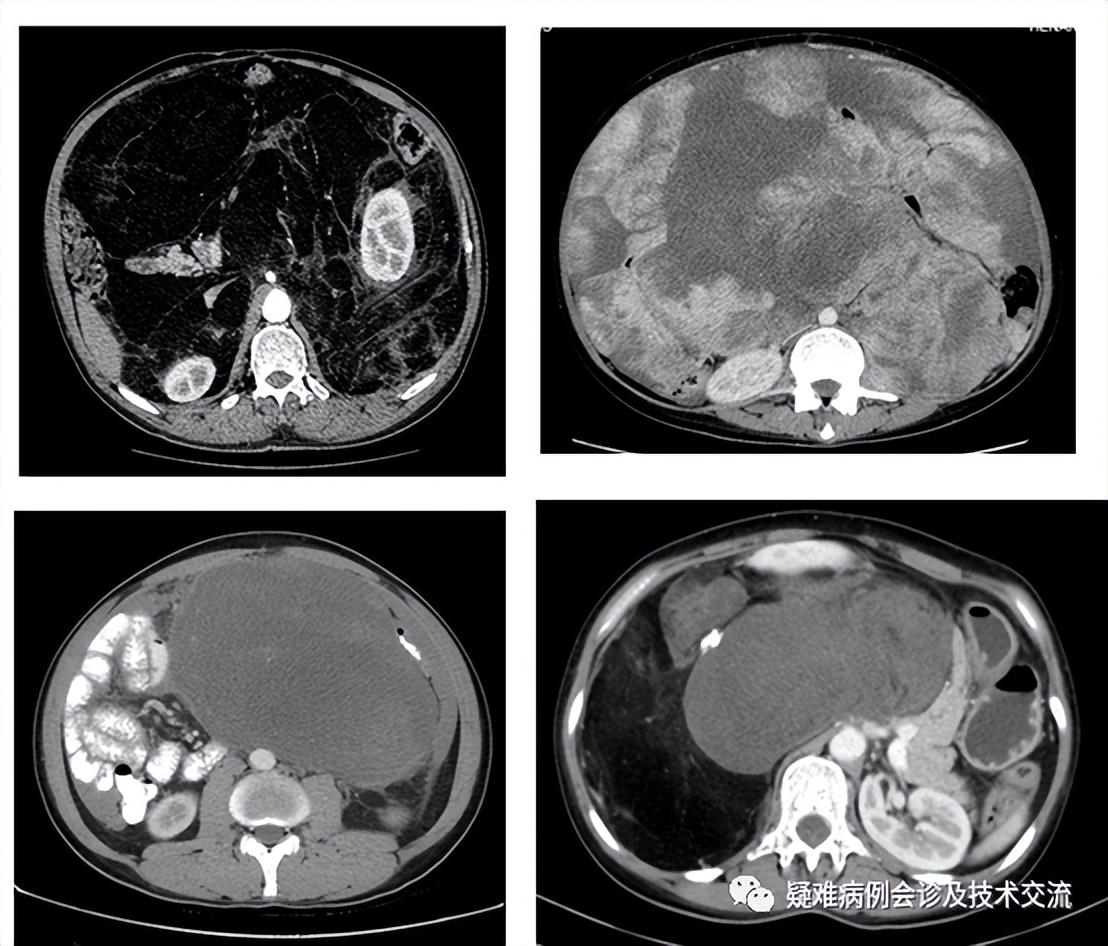

不同亚型脂肪肉瘤的CT表现

高分化:CT提示低密度,脂肪成分为主

多形性:CT密度值混杂不均,整个肿块不均匀强化

粘液性:CT提示肿瘤呈现水样密度,组织内含液性成分为主

去分化:CT提示肌肉样密度与脂肪样密度混合存在

本例特点:肿瘤位于右侧腹膜后,与十二指肠间隙清晰,主体右侧肾脏前方,判断为右侧肾前脂肪囊来源,CT值提示脂肪样密度,据此考虑为高分化脂肪肉瘤。此类肿瘤特点:包膜完整,质地柔软,一般不分叶存在,周围膜间隙清晰完整。